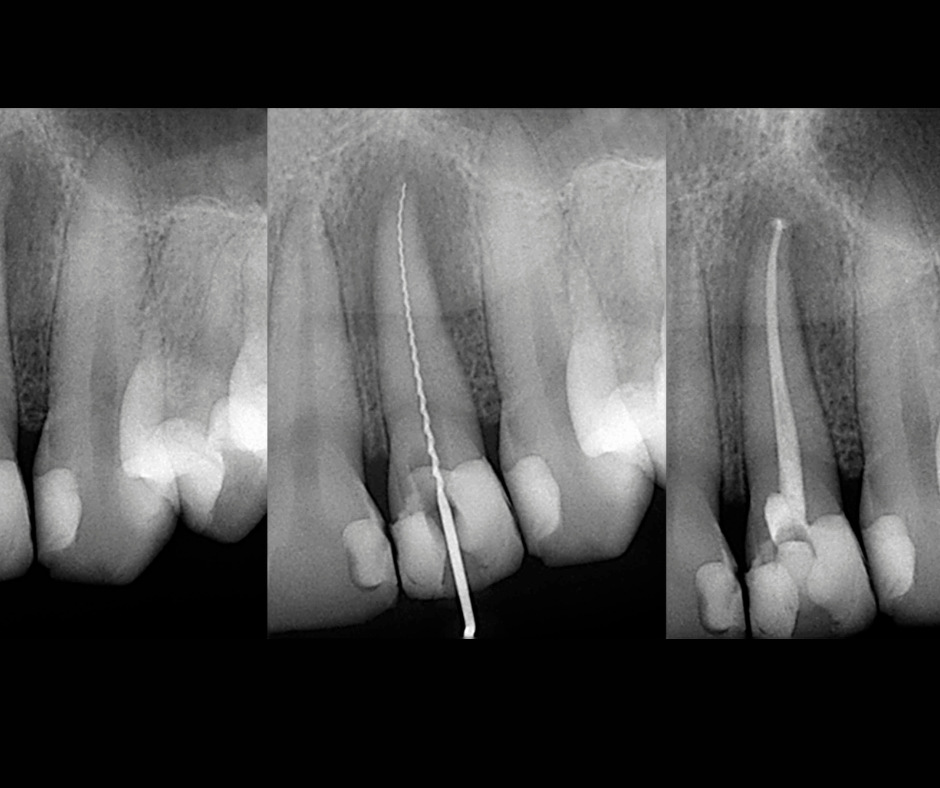

La endodoncia —conocida como “tratamiento de conducto”— es un procedimiento que permite salvar un diente afectado por infección, dolor o daño profundo.

2. ¿Cuánto dura el tratamiento?

Depende del diente y el caso, pero el procedimiento suele realizarse en una o pocas citas según la evaluación del especialista.